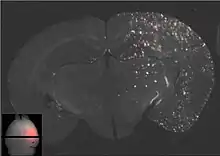

Les ultrasons peuvent être focalisés sur n'importe quel domaine du cerveau. C'est ainsi que l'on peut ouvrir la barrière hémato-encéphalique sélectivement sur des régions délimitées du cerveau. Les médicaments administrés pénétreront alors sur la zone ainsi ciblée[138]. On peut suivre le ciblage des zones par une IRM simultanée : il suffit d'administrer un produit de contraste IRM, comme du gadolinium convenablement chélaté, qui pénètre dans le cerveau à travers les parties de la barrière hémato-encéphalique ouvertes. Ces parties deviennent alors visibles en IRM. Les produits de contraste ne sont pas en mesure de franchir la barrière aux endroits où elle n'est pas ouverte.

Sur le modèle animal de la souris, on a utilisé des ultrasons focalisés dans le domaine de 0,5 à 2 MHz[139], avec de brèves impulsions de l'ordre de la milliseconde, répétées à intervalles de 1 s, pour une durée totale inférieure à une minute[140]. La fréquence optimale se situe au-dessous de 1 MHz[141]. La puissance acoustique instantanée est inférieure au watt, et donc la puissance moyenne de l'ordre du mW. Les microbulles utilisées sont en général des microbulles autorisées pour l'échocardiographie de contraste. Elles ont typiquement un diamètre de 3 à 5,5 μm, et sont composées typiquement d'albumine humaine, remplie d'octafluoropropane ou de gaz lourd semblable[142].